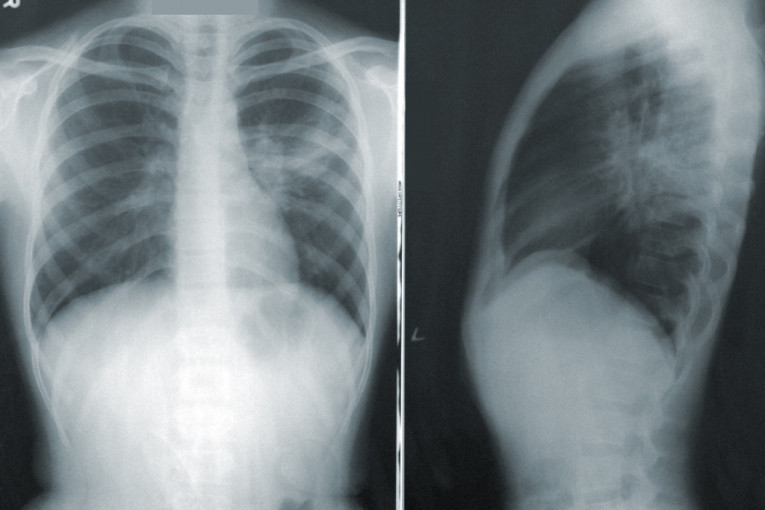

PET ZNAKOVA DA VAM OTKAZUJU PLUĆA: Telo vam šalje OVE signale koje ne smete da ignorišete!

Sveži vazduh je, nažalost, postao retkost, većina nas živi u onečišćenoj okolini, a to znači da više nego ikada trebamo da obratimo pažnju na signale koje nam pluća šalju